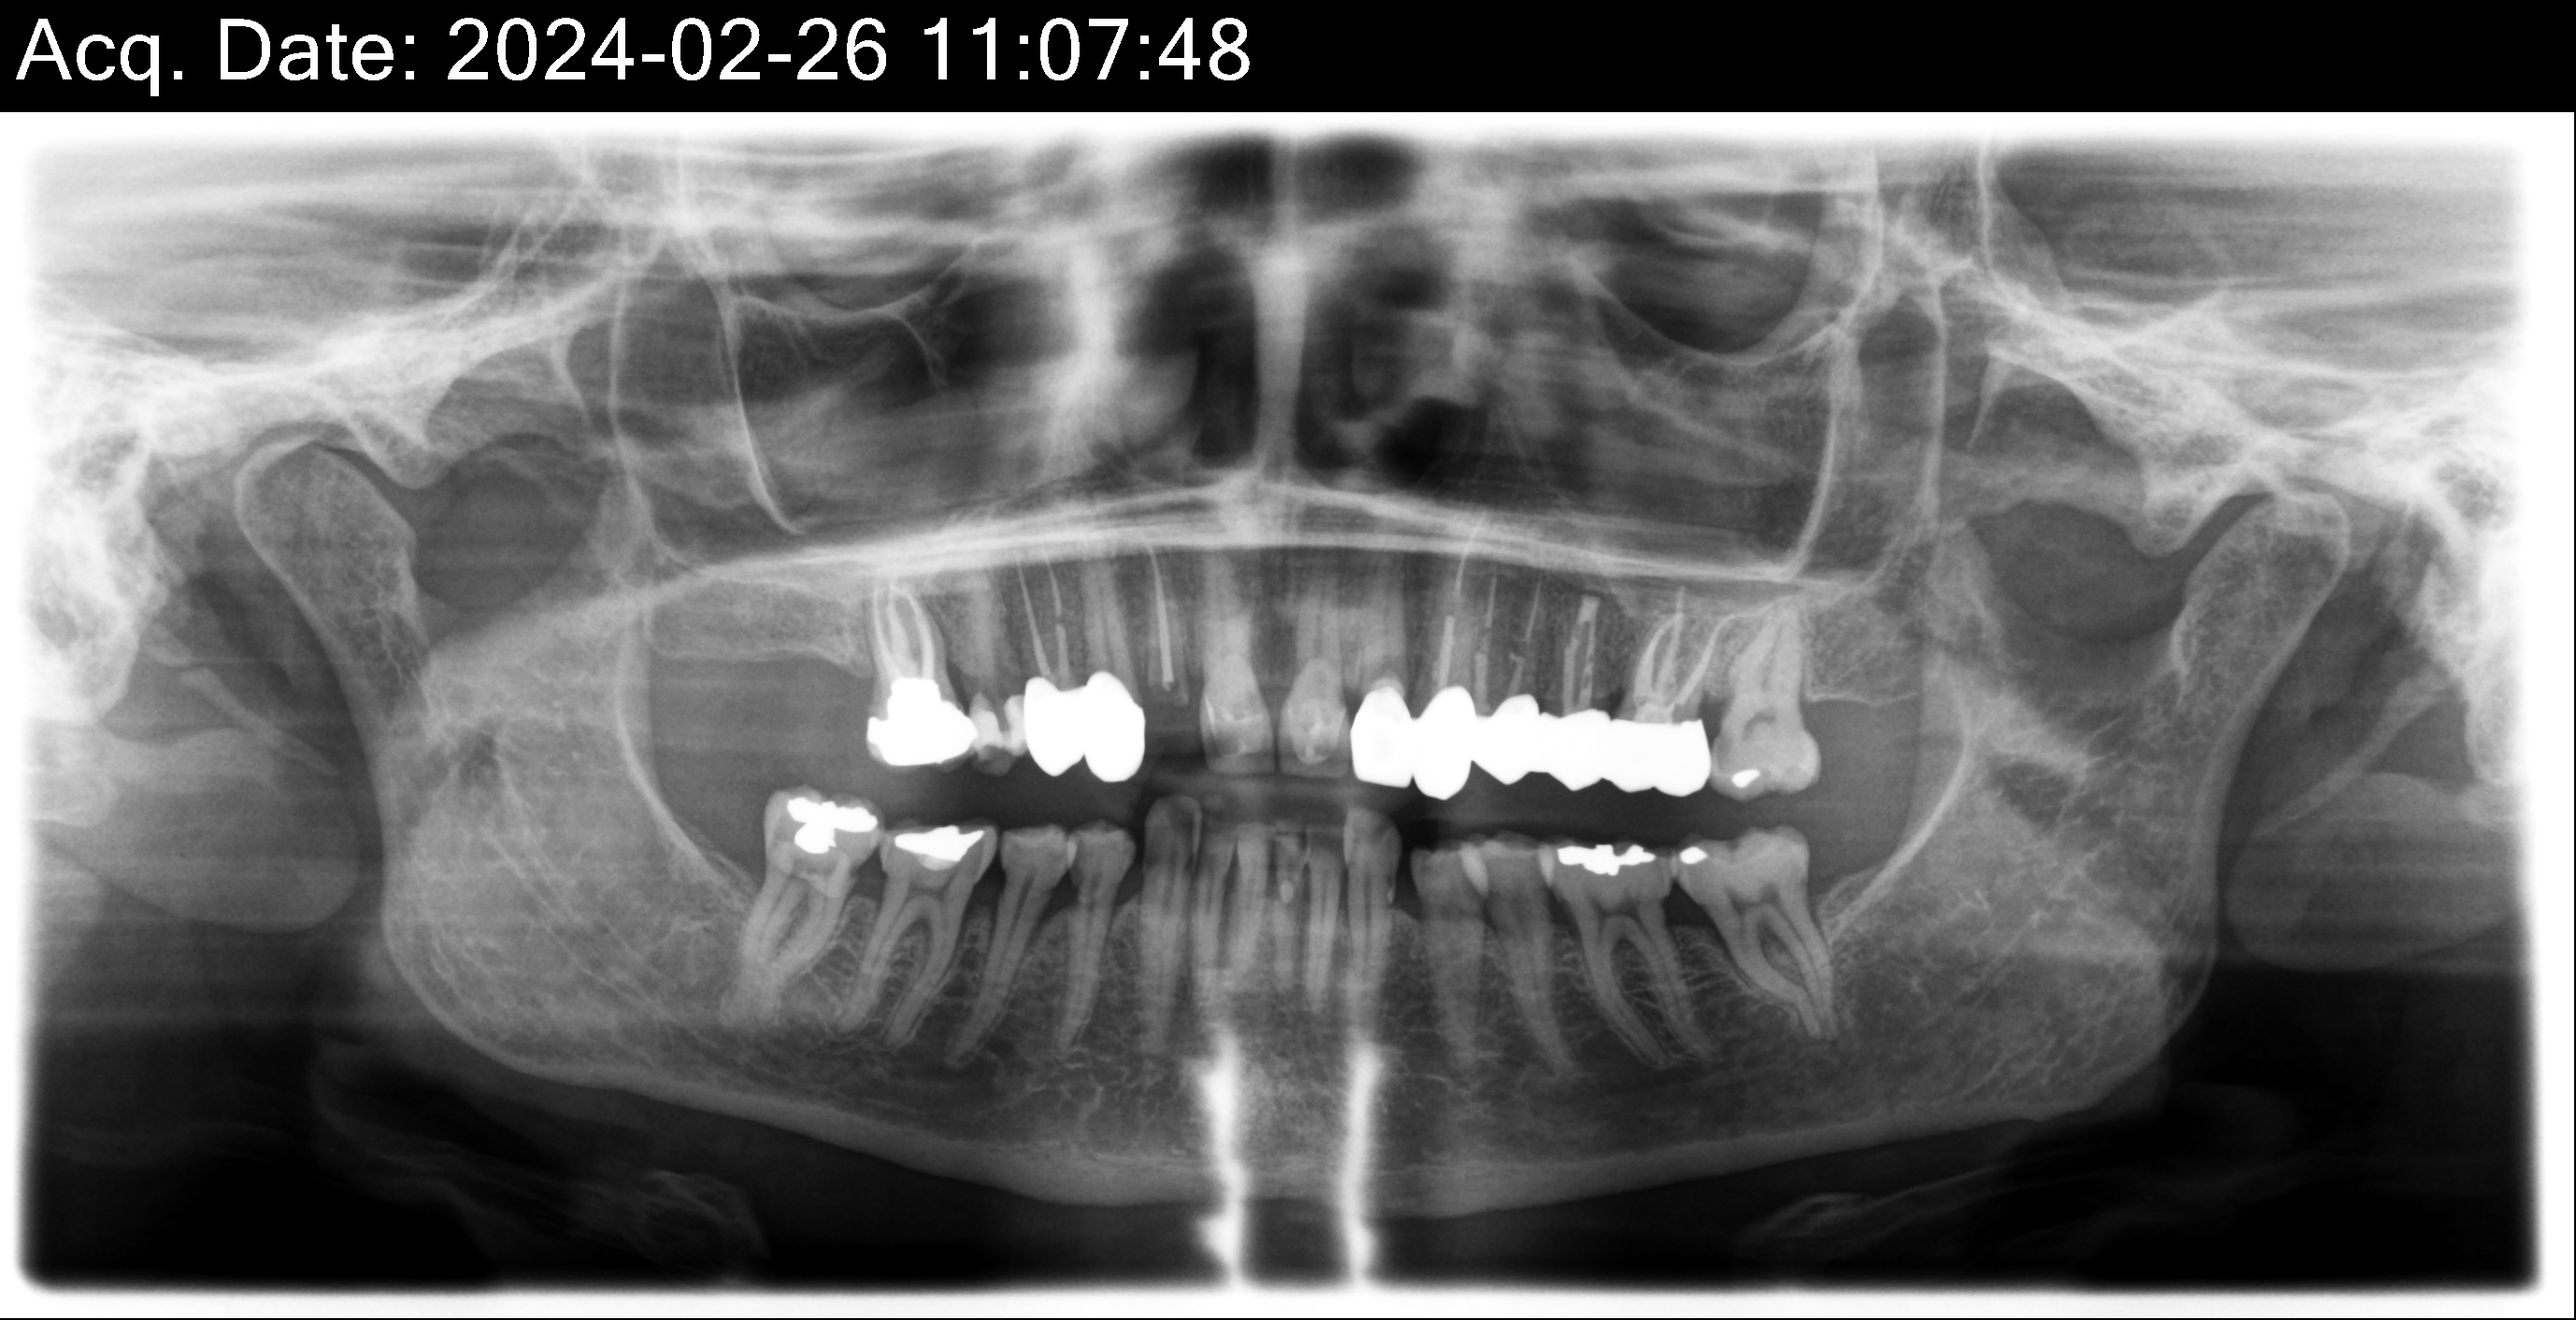

Overall information (upper arch)

12,13,14 have had root canals in past and now have quite a bit movement. 2-5 have all had root canals in past and now the crowns are breaking down.

Overall information (lower arch)

Overall, all of my gums have receded and most of the bottom teeth are exposed w/ some roots and there are many cavities.